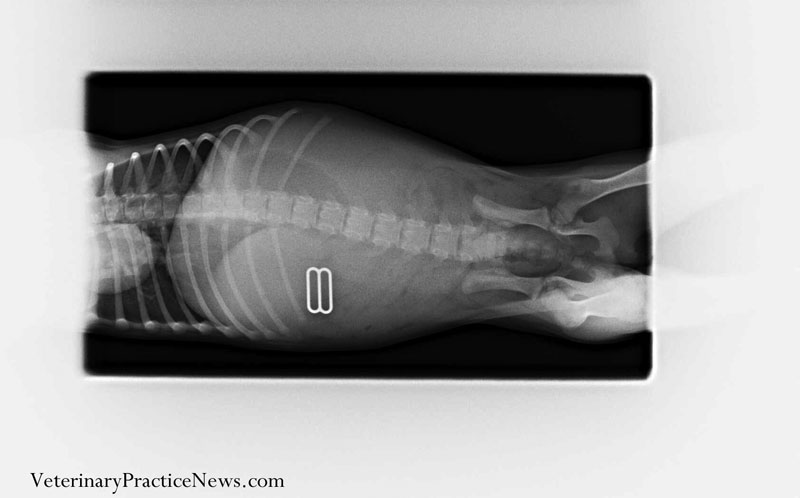

最後一個是,吞下女主人胸罩的獵鼠梗犬,不得了,這種梗犬活潑好動,只是追獵物怎會把主人的內衣都喀了?從X光片裡發現內衣的環扣證實是被吞下肚,而經由胃及小腸的手術也順利取出內衣殘骸,從此牠再也不准進去洗衣間了。